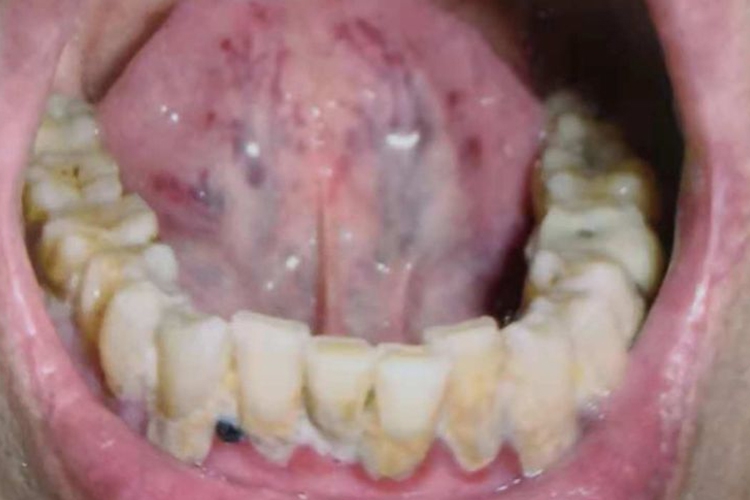

中医常用望诊,观察舌底的状态,常见的舌底异常表现为舌底瘀丝、舌底瘀点瘀斑、紫暗舌底。

舌底瘀丝:可见舌底细小脉络呈网状扩散或伞形曲张,其色青紫,甚则脉络间有瘀点。常见于各种瘀血证。

舌底瘀点瘀斑:可见舌底颜色红暗,舌底两侧及舌尖不由紫暗瘀点。常见于瘀血、热盛动血等病症。

紫暗舌底:可见舌面颜色正常,舌底颜色青紫,并有脉络曲张或瘀丝瘀点,常见于各种瘀血证。